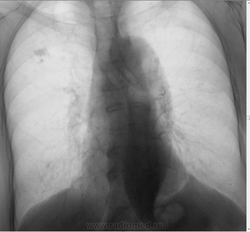

Уважаемые коллеги прошу вашей помощи. Женщина 1937 года, направлена уч. терапевтом с предварительным диагнозом - пневмония. Снимки с 2010 - по 2012 год. Из архива 2010-2011 "НА ВЕРХУШКАХ ОБЕИХ ЛЕГКИХ -ПЛ. ОЧАГИ.Р+". Что можете сказать по поводу 2012 года?

Насколько мне видно-"подсыпало" с плотного очага и лимфогенная диссеминация имеется. Хотите покрутить-томо серединный срез,а далее по обстоятельствам. Не хотите заниматься-отправляйте к фтизиатрам.

динамика отрицательная. отправил бы к фтизиатрам.

Однозначно, рецидив ТБ. Диссеминированный.

Очень даже похоже на рецидив туберкулеза. Вот только бы еще с этой "пневмонией" до конца разобраться...какова клиника по вашему?

+1 За туберкулез